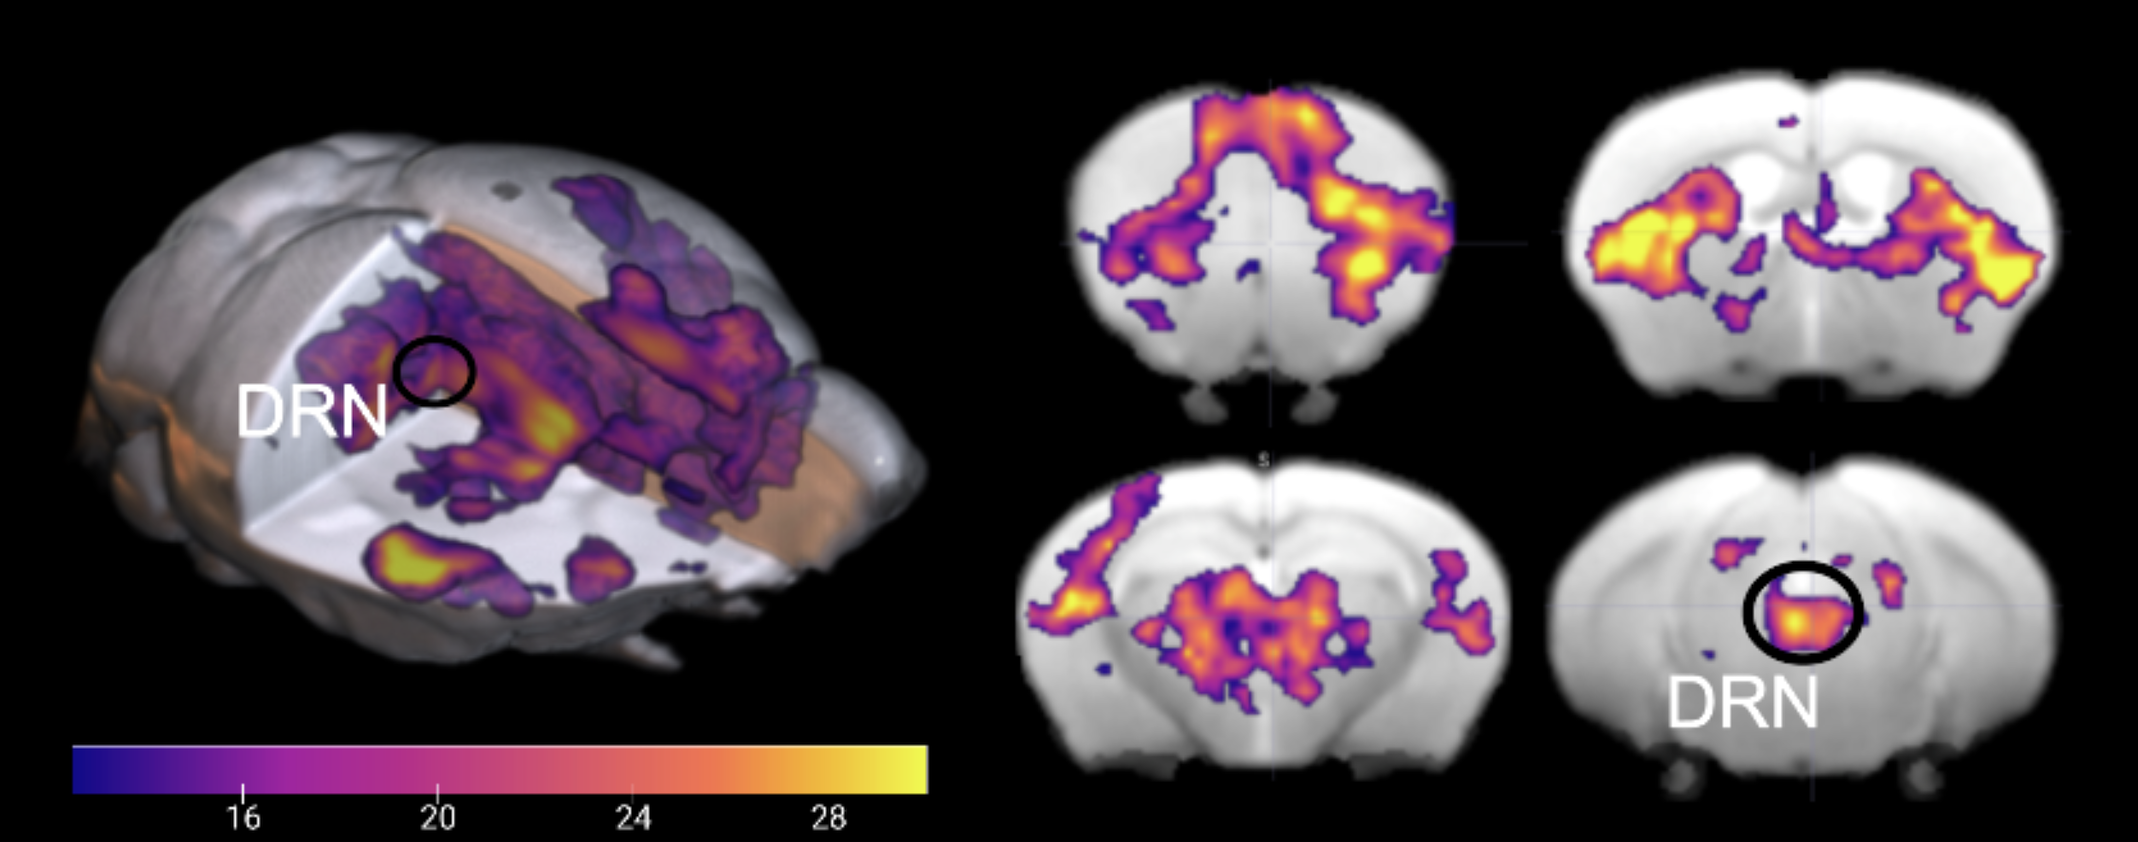

覚醒状態で背側縫線核を刺激したときの脳の活性化の様子

覚醒状態において、背側縫線核のセロトニンニューロンを光で刺激すると、脳の特定の部位が異なる強度で活性化する。画像提供:Hamadaら, 2024年